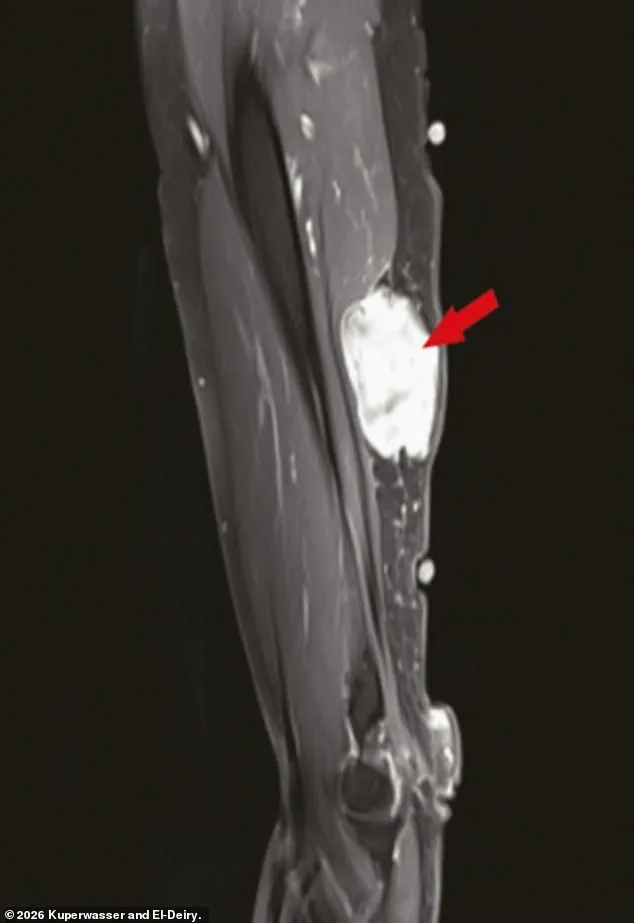

Notably, many of the cases involved tumors near injection sites in the arm, a detail that has fueled speculation about a possible connection between the vaccine and malignancies.

Some case reports referenced in the review described localized reactions near injection sites, prompting the authors to call for further investigation into potential biological mechanisms that might explain these observations.